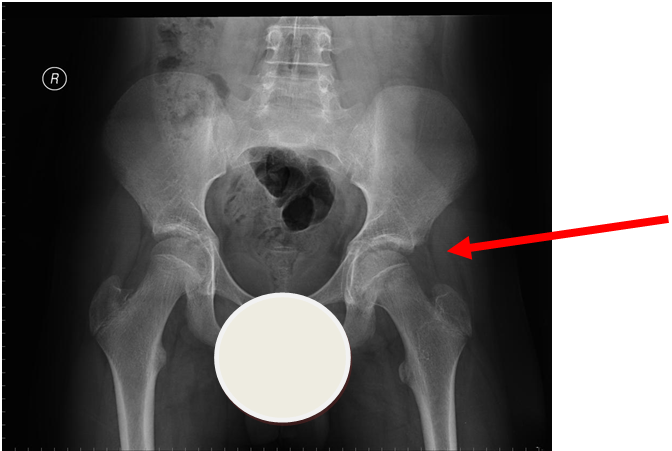

4. Slipped Upper Femoral Epiphysis (SUFE)

Subtle left sided SUFE.

Case courtesy of Dr Gagandeep Singh, Radiopaedia.org. From the case rID: 7688

Usually occurs in late childhood / adolescence and is more common in boys than girls (2:1). It also presents more commonly in children whose weight is above the 90th centile. Bilateral in 25% of cases. Onset can be acute or subacute (ie children may present with >1day h/o pain or limp). Children may walk with an antalgic gait out-toeing, with shortening of the affected limb. If the slip is acute, the child may be unable to walk. Diagnosis is made radiologically and frog-lateral views are required as it may be missed on AP views. Urgent orthopaedic opinion is required. Unstable slips can lead to avascular necrosis of the femoral head.

Investigation

- X-ray - AP pelvis with frog lateral view (must be discussed with ortho 1st on call / ED consultant if child <8 years old)